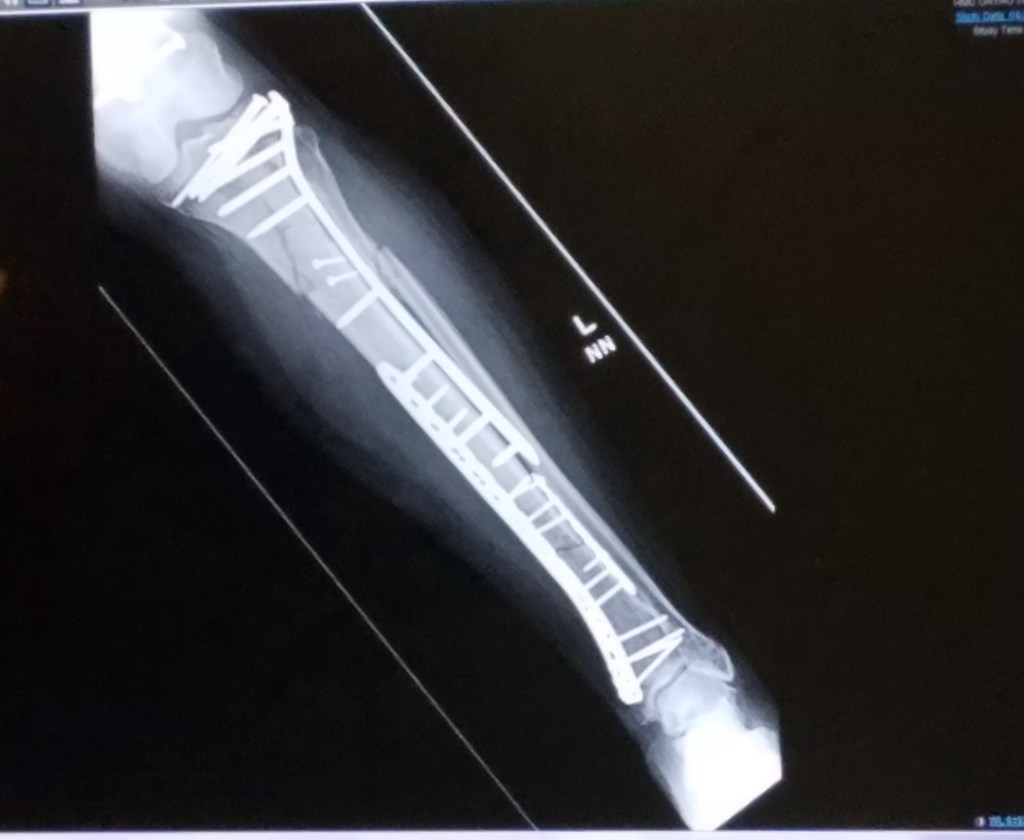

Zooming in on this week’s x-rays, I can see the top half of my tibia was completely separated. And I know the large puncture wound on the front of my shin was the result of the bone poking through the skin. I want to trust the plate and ten pins along with the three long screws holding it together, but it’s difficult, seeing the extent of the break.

Below this plate “assembly” are two more plates with their own collection of 13 pins and screws. Altogether, my badly mangled tibia is held together with 3 plates, and 25 pins and screws. My fibula, which was snapped in half, wasn’t fixed, and is somewhat knitted together. Supposedly, it’s not weight bearing.

Until Wednesday, I pretended to “see” the x-rays. This week, I snapped pictures with my smart phone to better understand what comprises the erector set, which is the superstructure now holding my leg together. Maybe denial was healthier. I could amuse myself with the fantasy that starting to walk was going to be a breeze.